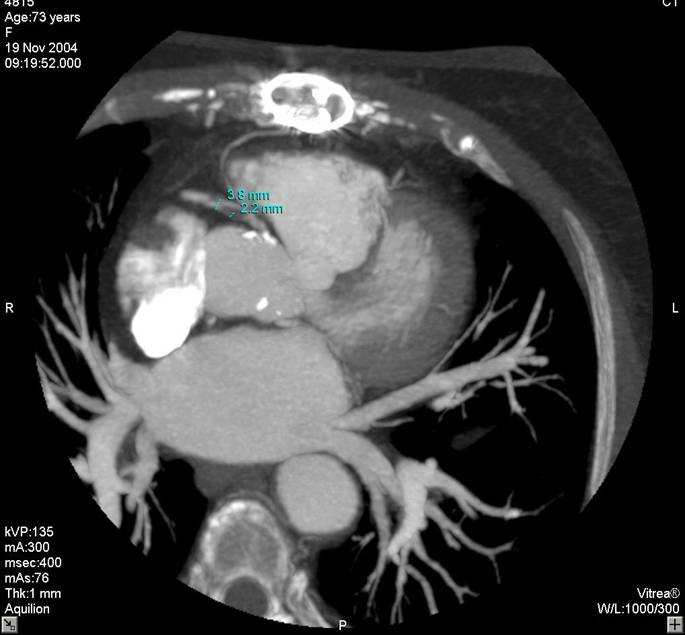

The non-invasive imaging modality of multi-detector computed tomography has dramatically evolved the last ten years and that is due to hardware and software developments. The newer generation of scanners allows increased spatial and temporal resolution that improves the clinical reliability giving further insights into the evaluation of coronary artery disease. Heart morphology imaging followed by studies of myocardial function and assessment of cardiac valves can be performed from the information derived from the data of the coronary artery examination. Also, the venous anatomy of the heart, coronary artery bypass grafts, stents, and cardiac tumors can be imaged and evaluated when necessary. For the beneficial use of this method, entrance criteria for different patient groups need to be set in order to allow improved outcome of multi-detector CT.